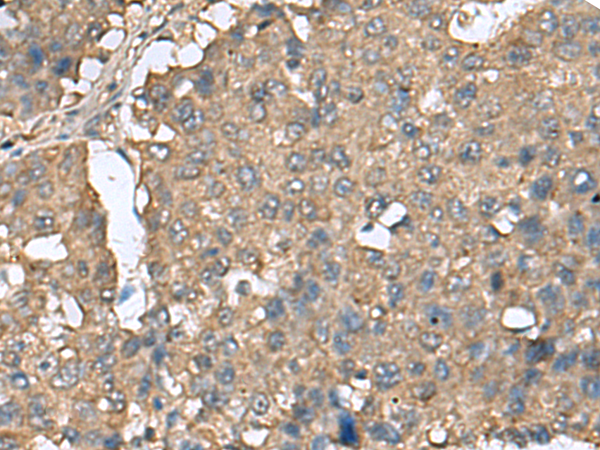

IHC positive control: |

Human liver cancer and Human esophagus cancer |

IHC Recommend dilution: |

50-200 |